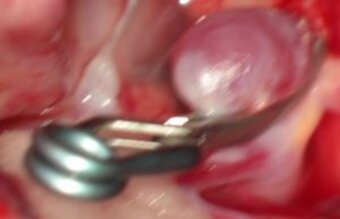

Aneurysm: The microsurgical treatment by clipping

Clipping is an open microsurgical surgery, a skull opening, called craniotomy is being performed under general anesthesia. Under the surgical microscope, the aneurysm is located and isolated from the supprt vessel with the help of a titanium clip. The bone flap is being reattached to the skull, the wound is being closed.

Advantage of the clipping: By clipping out the aneurysm under direct vision a control angiography is rarely necessary.

Disadvantage of clipping: The necessary opening of the skull.